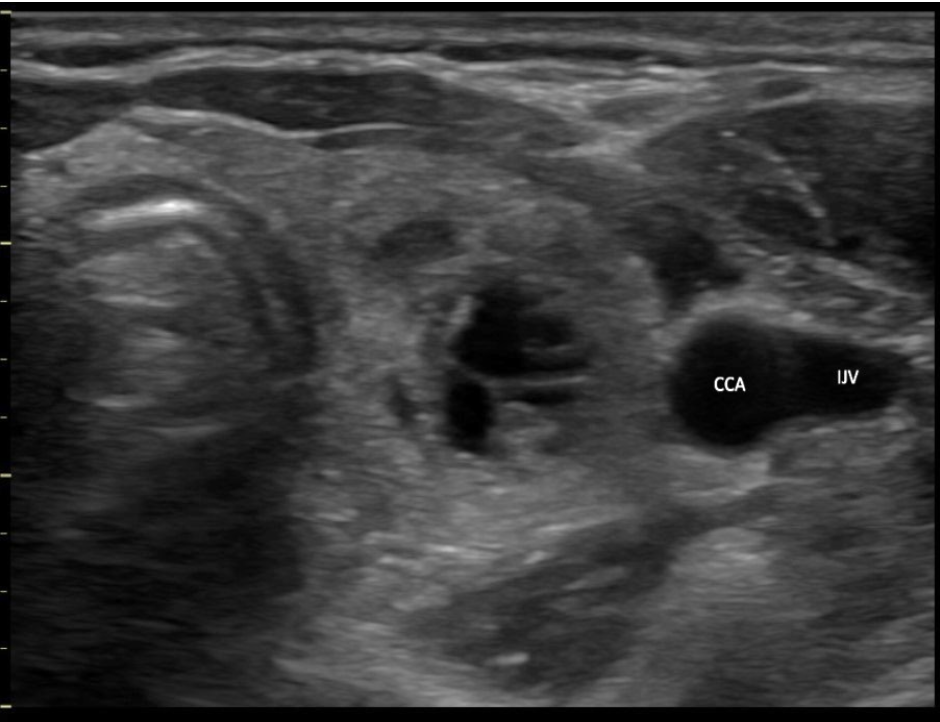

Which blood vessel is located lateral to the left lobe of the thyroid and demonstrates an anechoic ovoid shape in a transverse view of the mid thyroid?

B. left internal jugular vein

The internal jugular vein is located lateral to the left lobe of the thyroid and demonstrates an anechoic ovoid shape in a transverse view of the mid thyroid. The carotid artery is also lateral to the thyroid lobes but it should be a circular structure.

The image displays the left lobe of the thyroid with the circular CCA immediately lateral to the mid lobe and ovoid IJV lateral to the CCA.

Which blood vessel is located lateral to the right lobe of the thyroid and demonstrates an anechoic circular shape in a transverse view of the mid thyroid?

C. right common carotid artery

The right common carotid artery is located lateral to the right lobe of the thyroid and demonstrates an anechoic circular shape in a transverse view of the mid thyroid.